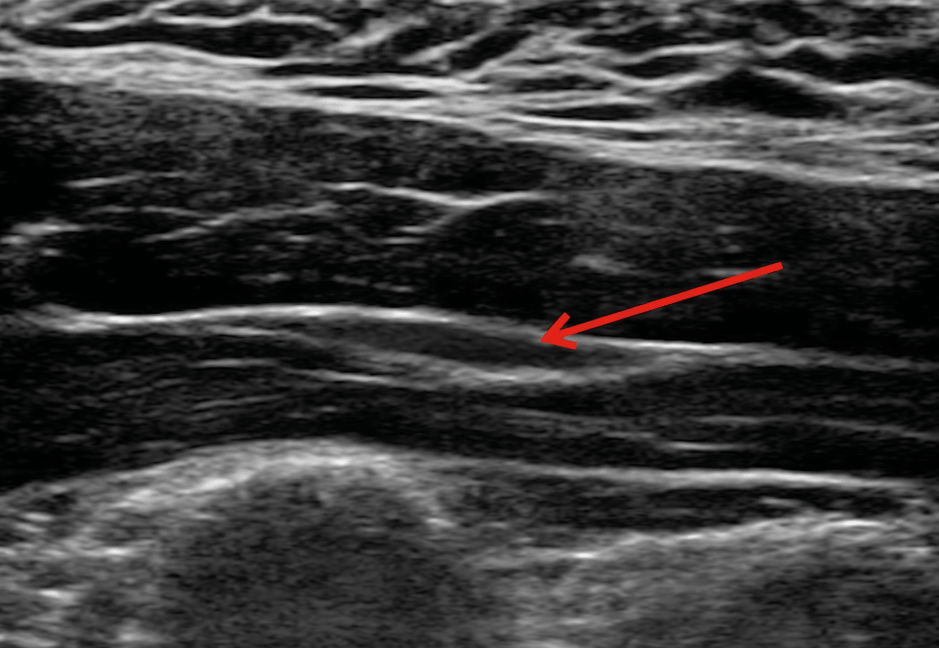

医師の手探りではなく、最新の超音波エコー装置を使って、皮膚の下の「筋膜が白く癒着している部分(痛みの原因)」をミリ単位で正確に見つけ出します。

1)筋膜の癒着で血行の悪くなった筋繊維がコリや痛みの原因となります。2,3)注射で癒着を剥離すると、直ちに症状が改善することが多いです。